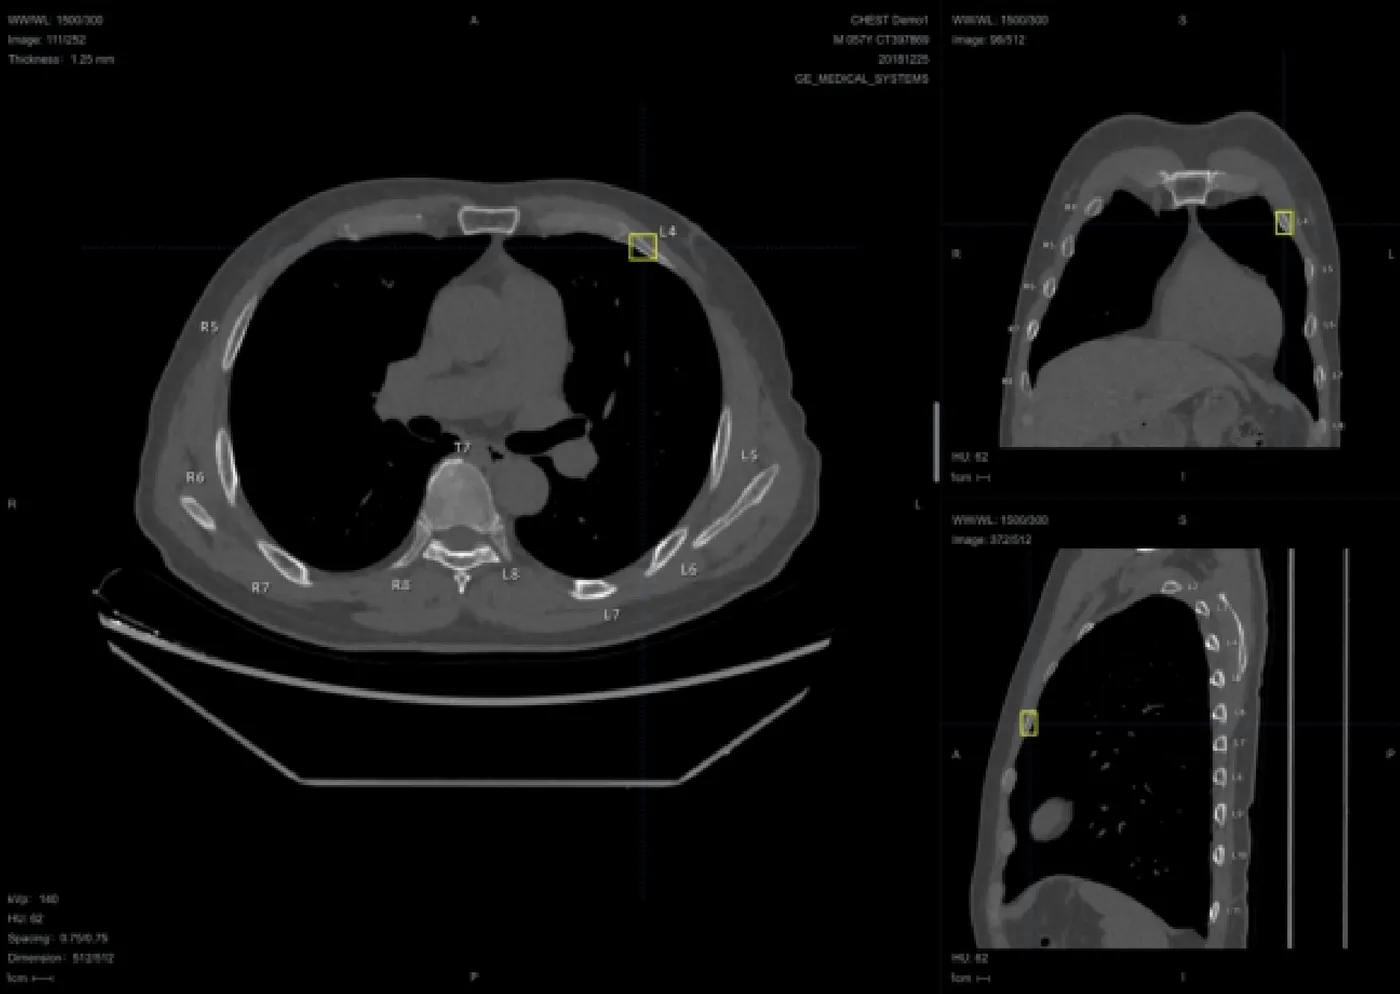

- 🩻 核心PACS阅片引擎 (Web Viewer)

极速加载引擎: 采用按需加载与无损压缩传输技术,即使在普通宽带下也能实现大序列CT图像的“边下边看”。

专业影像处理工具包:

基础操作: 无级缩放、漫游、旋转、翻转、放大镜。

专业调节: 自定义窗宽窗位(支持预设腹部、骨骼、肺部等模式)、伪彩渲染。

精准测量: 长度、角度、面积、CT值(HU值)测量、心胸比自动计算。

🌟 高级三维重建 (硬核卖点): 纯前端实现 MPR (多平面重建)、CPR (曲面重建)、MIP (最大密度投影)、VR (容积渲染),媲美传统工作站的渲染效果。

影像对比与序列协同: 支持多屏多序列同步滚动阅片,方便随访复查对比。